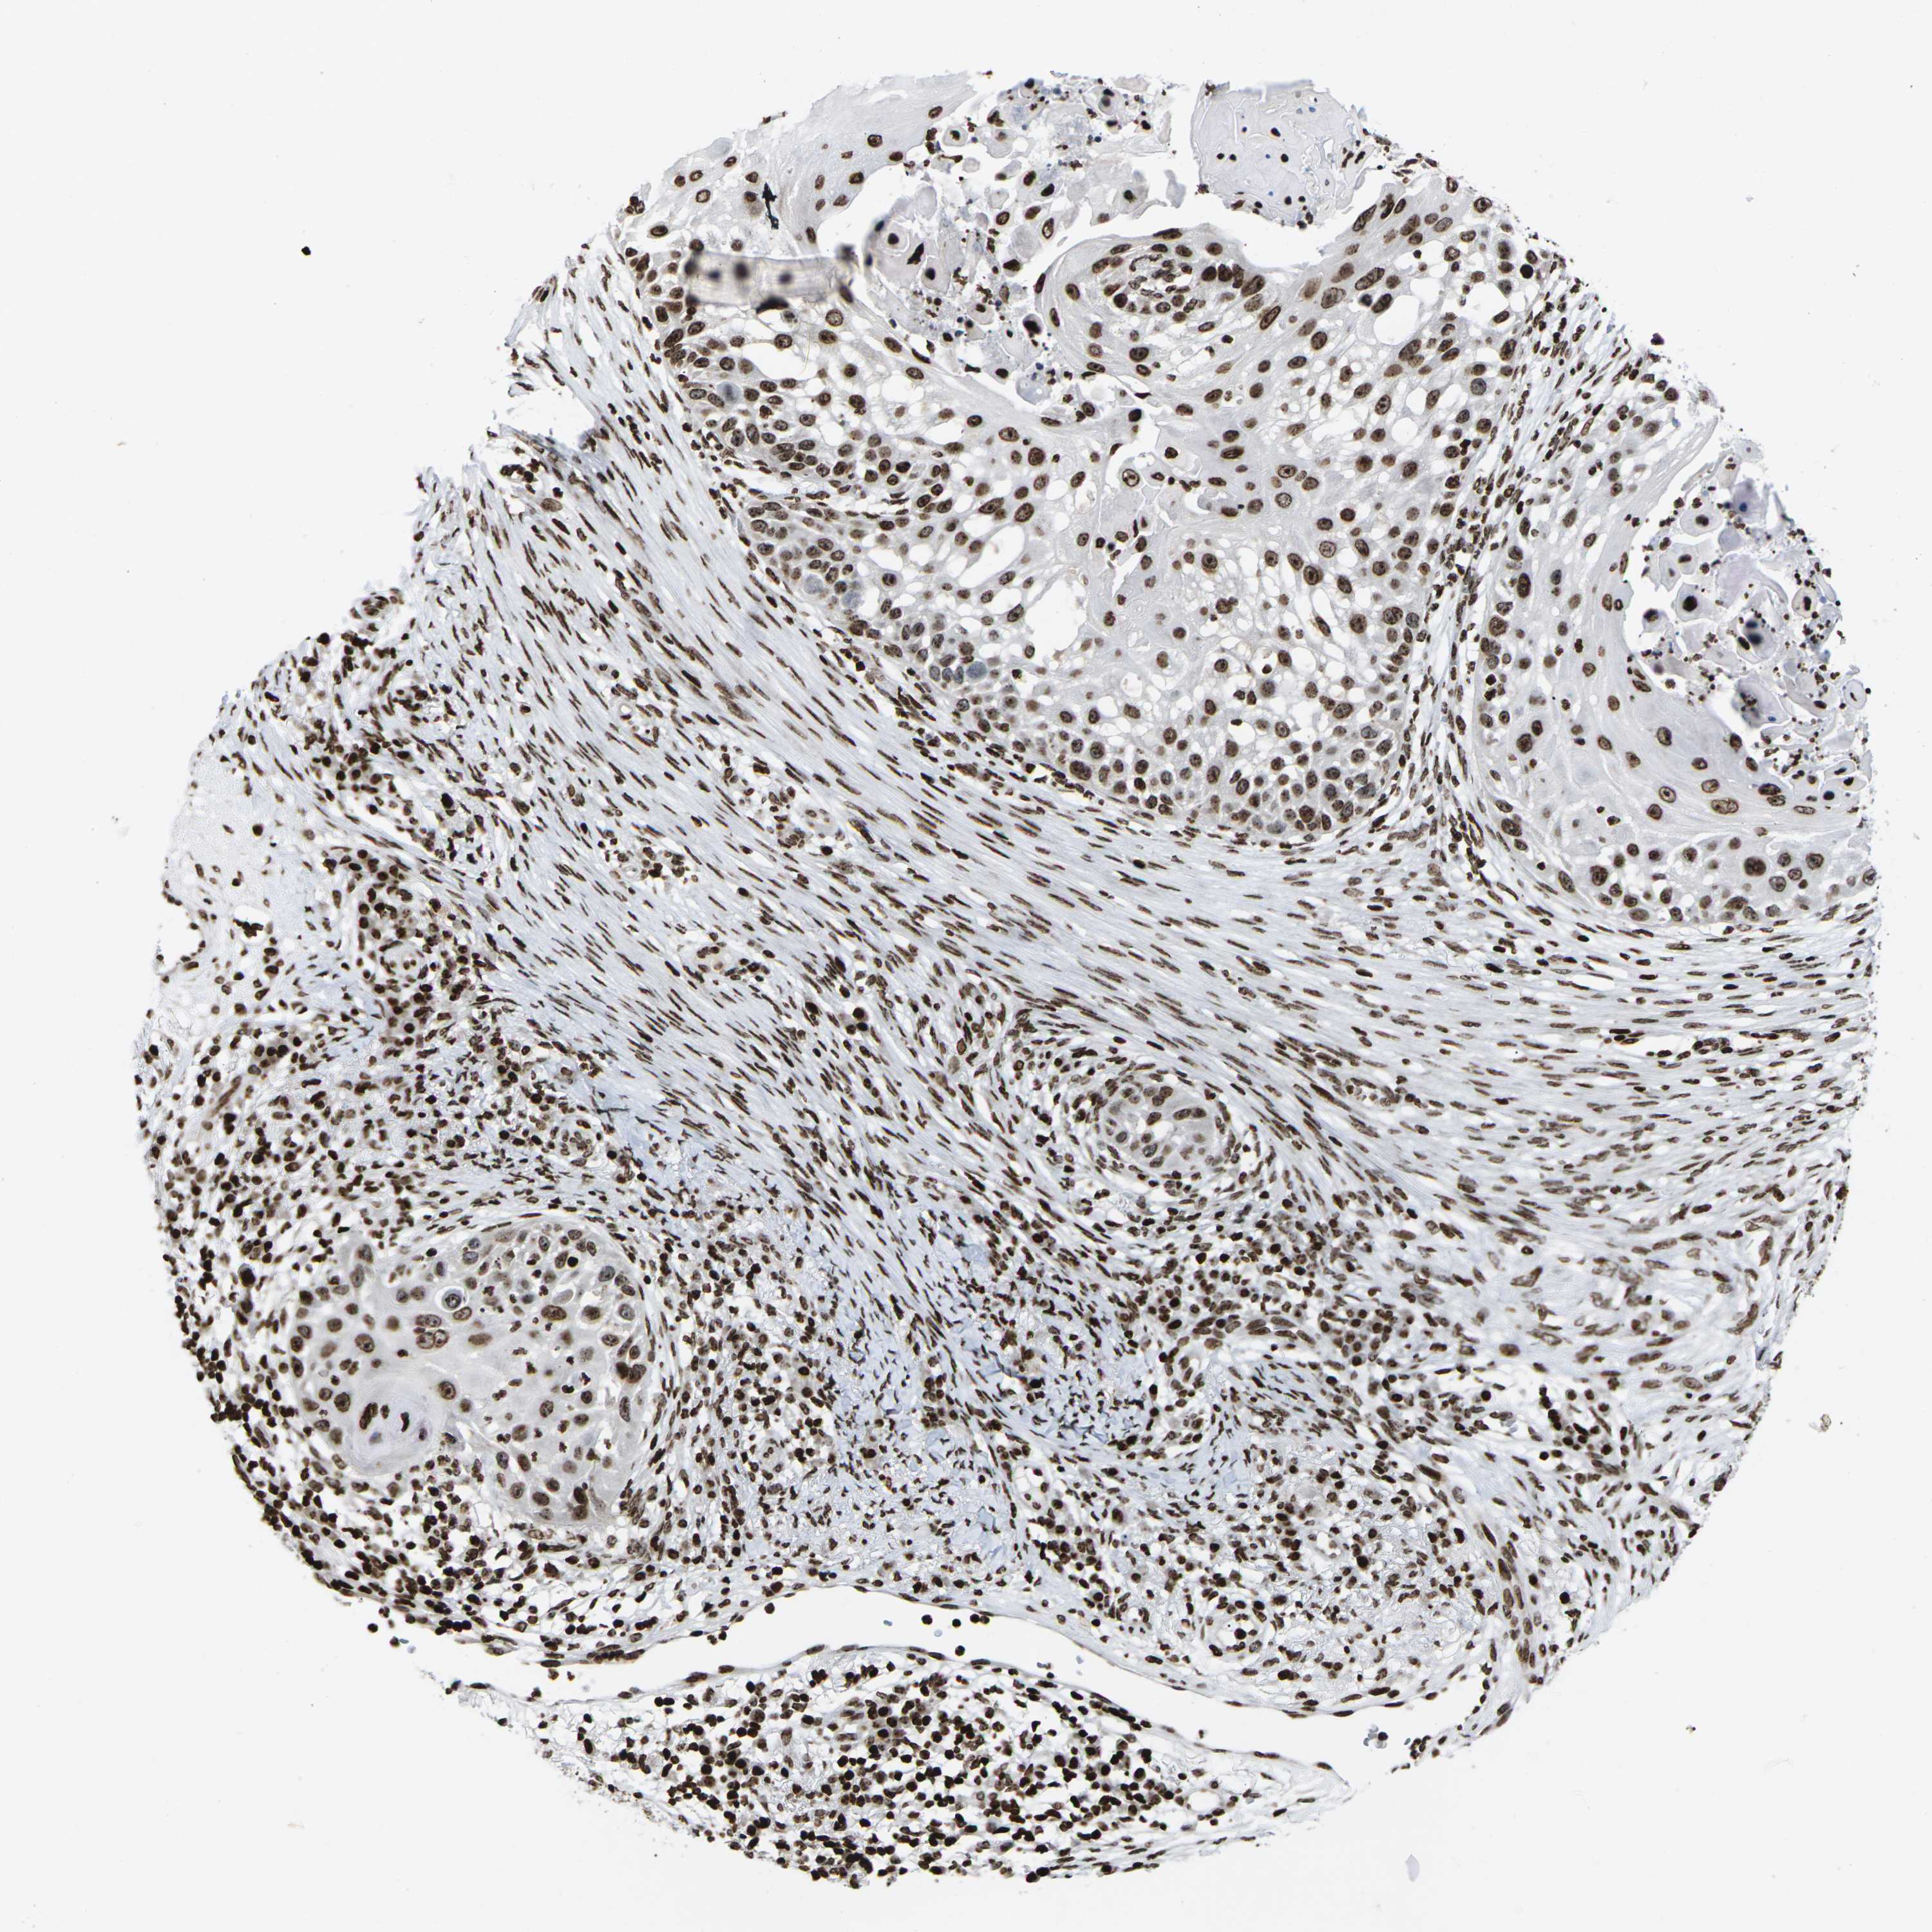

SKIN CANCER - Protein expressioni

A mouse-over function shows sample information and annotation data. Click on an image to view it in a full screen mode. Samples can be filtered based on level of antibody staining by selecting one or several of the following categories: high, medium, low and not detected. The assay and annotation is described here.

Each image is clickable and will lead to virtual microscopy that enables deeper exploration of all samples and also displays staining intensity scores, fraction scores and subcellular localization as well as patient and tissue information for each sample.

Antibody HPA055907

Basal cell carcinoma